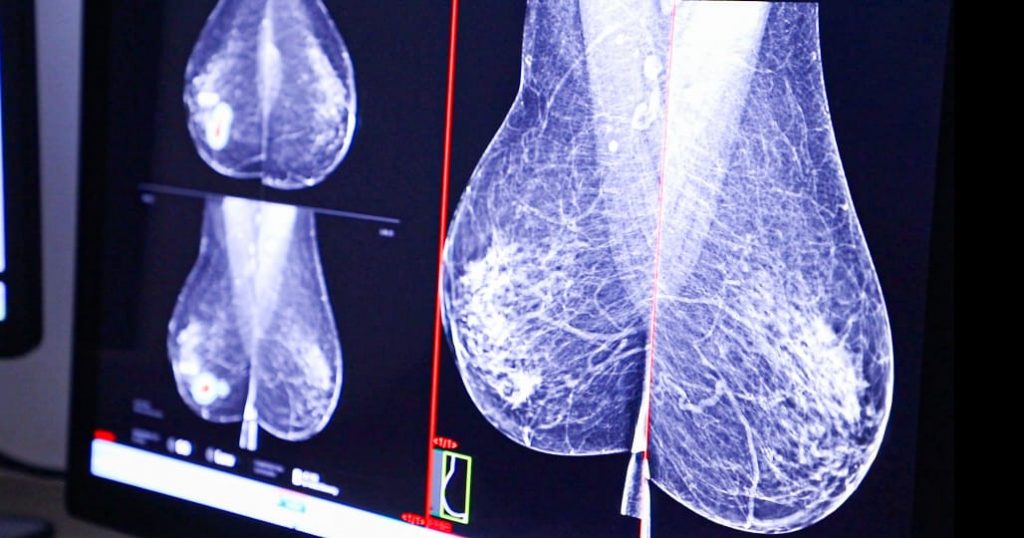

CSS estrena dispositivo para marcación precisa de lesiones en cáncer de mama

La Caja de Seguro Social (CSS) continúa fortaleciendo su capacidad de diagnóstico y tratamiento del cáncer de mama mediante la incorporación de técnicas modernas y seguras.

Recientemente, la institución inició el uso de un reflector, un pequeño marcador que permite identificar con alta precisión lesiones o tumores antes de la cirugía, mejorando la planificación y los resultados quirúrgicos.

Este dispositivo, de tamaño similar a un grano de arroz, fue implantado por primera vez en una paciente de 63 años de edad en el Centro de Imágenes Médicas Avanzadas de la Ciudad de la Salud. El procedimiento fue realizado por el equipo de la Unidad de Imágenes Mamarias de la CSS.